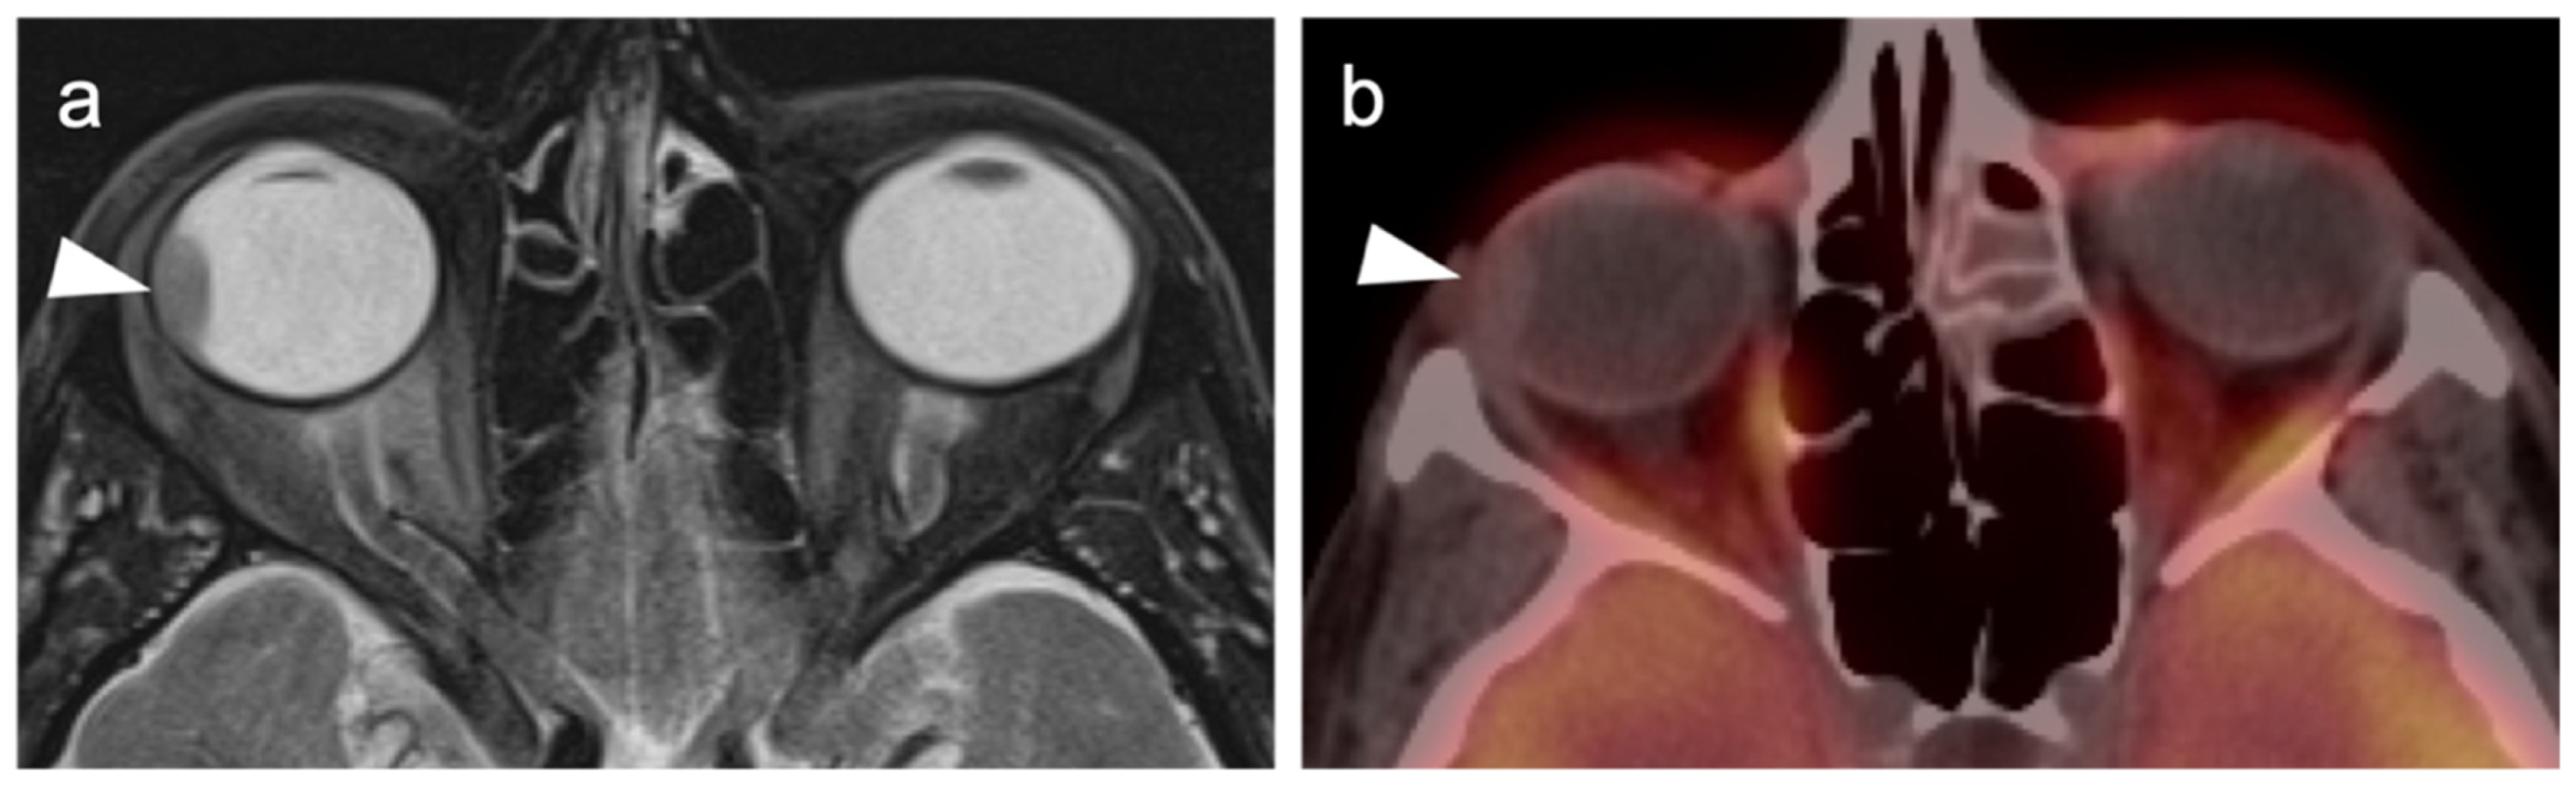

2.3.2. Ocular Melanoma

- Sharma, R.; Shah, P.; Narendran, V. Poor uptake of fluorodeoxyglucose in positron emission tomography-computed tomography scan for intraocular choroidal melanoma in Asian Indian Eyes. World J. Nucl. Med. 2016, 15, 53–55. [Google Scholar] [CrossRef]

- Reddy, S.; Kurli, M.; Tena, L.B.; Finger, P.T. PET/CT imaging: Detection of choroidal melanoma. Br. J. Ophthalmol. 2005, 89, 1265–1269. [Google Scholar] [CrossRef] [Green Version]

- Zurcher, K.S.; Houghton, O.M.; Shen, J.F.; Seetharam, M.; Roarke, M.C.; Yang, M. Nuclear Medicine and Molecular Imaging in Nodal Staging and Surveillance of Ocular Melanoma: Case Reports and Review of the Literature. J. Nucl. Med. Technol. 2021, 49, 275–280. [Google Scholar] [CrossRef]